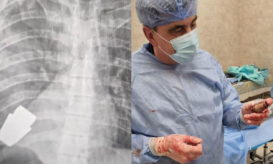

Η οπλοβομβίδα δεν είχε σκάσει, ήταν όμως "ζωντανή" και είχε σφηνώσει δίπλα στην καρδιά του!